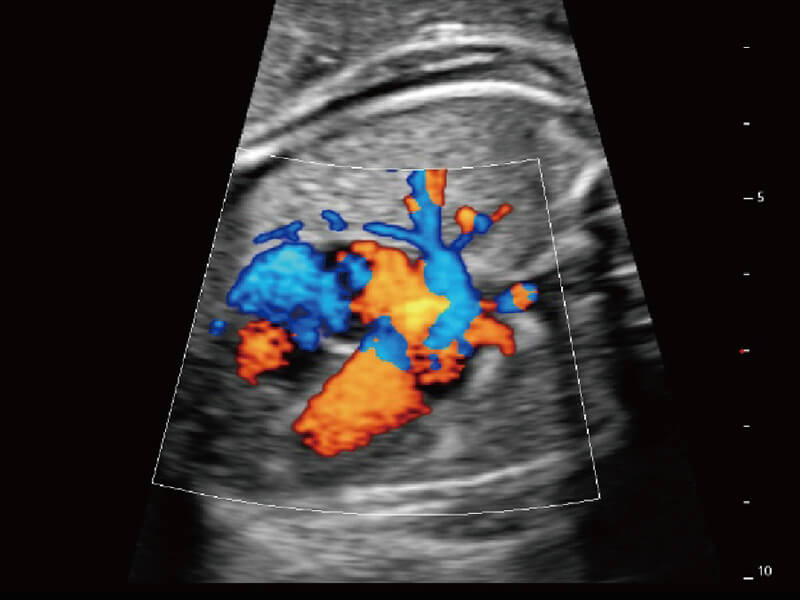

彩色多普勒超声诊断系统

S60探头工艺,从前端信号处理每一个环节采集无损声学数据,真实还原组织原貌,再现解剖细节。

超宽频带技术,为容积成像带来优质的二维图像基础,为您呈现丰富的结构细节,栩栩如生地展示宝宝的宫内形态以及各种组织的立体结构。